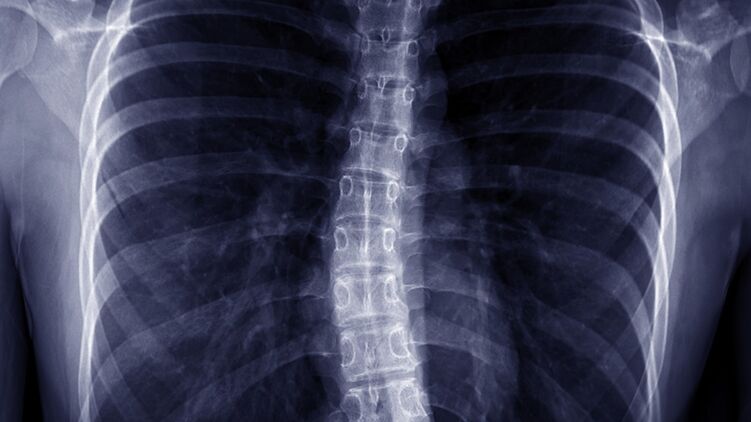

Этот недуг характеризуется S или C образным искривлением позвоночника в боковой плоскости. Человек может выглядеть так, будто он наклоняется в одну сторону. При этом могут поражаться как грудной, так и поясничный отдел позвоночника.

С увеличением искривление растет тенденция к ухудшению проблем общего состояния здоровья. Сильные сколиозы является причиной деформации туловища и его укорочения и приводят к уменьшению объема грудной клетки и брюшной полости.

- заметно изогнутый позвоночник, склонен в одну сторону

- одна лопатка выступает больше, чем вторая

- неравномерность формы грудной клетки сзади при наклоне туловища вперед

- выпячивание ребер с одной стороны

- при тяжелых формах грудная клетка может сдавливать легкие и сердце, что затрудняет дыхание и сердечную деятельность